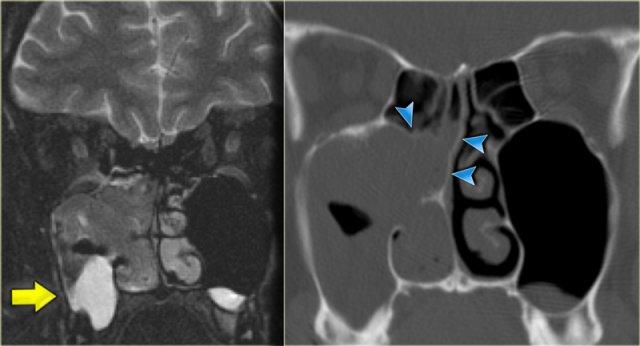

Bên trái là một trường hợp ban đầu được chẩn đoán nhầm là khối u.

Có vật chất tăng tỷ trọng ở xoang sàng sau bên phải, các ngách bướm-sàng hai bên, xoang bướm và có sự xâm lấn vào xương nền sọ (clivus).

Tình trạng tăng tỷ trọng là dấu hiệu tiên lượng tốt, gợi ý một quá trình lành tính.

Đây là ví dụ điển hình của viêm xoang nấm dị ứng.

Thông thường tổn thương này có vị trí ở phía trước hơn.

Bên trái là một ví dụ khác, điển hình hơn, của viêm xoang nấm dị ứng.

Có hình ảnh mờ đục hai bên hốc mũi, thường là dấu hiệu của quá trình viêm hoặc polyp.

Lưu ý hình ảnh phân lớp đồng tâm xen kẽ giữa tăng tỷ trọng và giảm tỷ trọng trong các xoang hàm.

Tình trạng tăng tỷ trọng là do dịch tiết đặc quánh và các thành phần nấm.

Tình trạng giảm tỷ trọng phản ánh các nang, bệnh lý niêm mạc và mô hạt.

Ở vùng xoang sàng, một phần tình trạng tăng tỷ trọng phản ánh viêm màng xương và tân tạo xương dọc theo các vách ngăn.